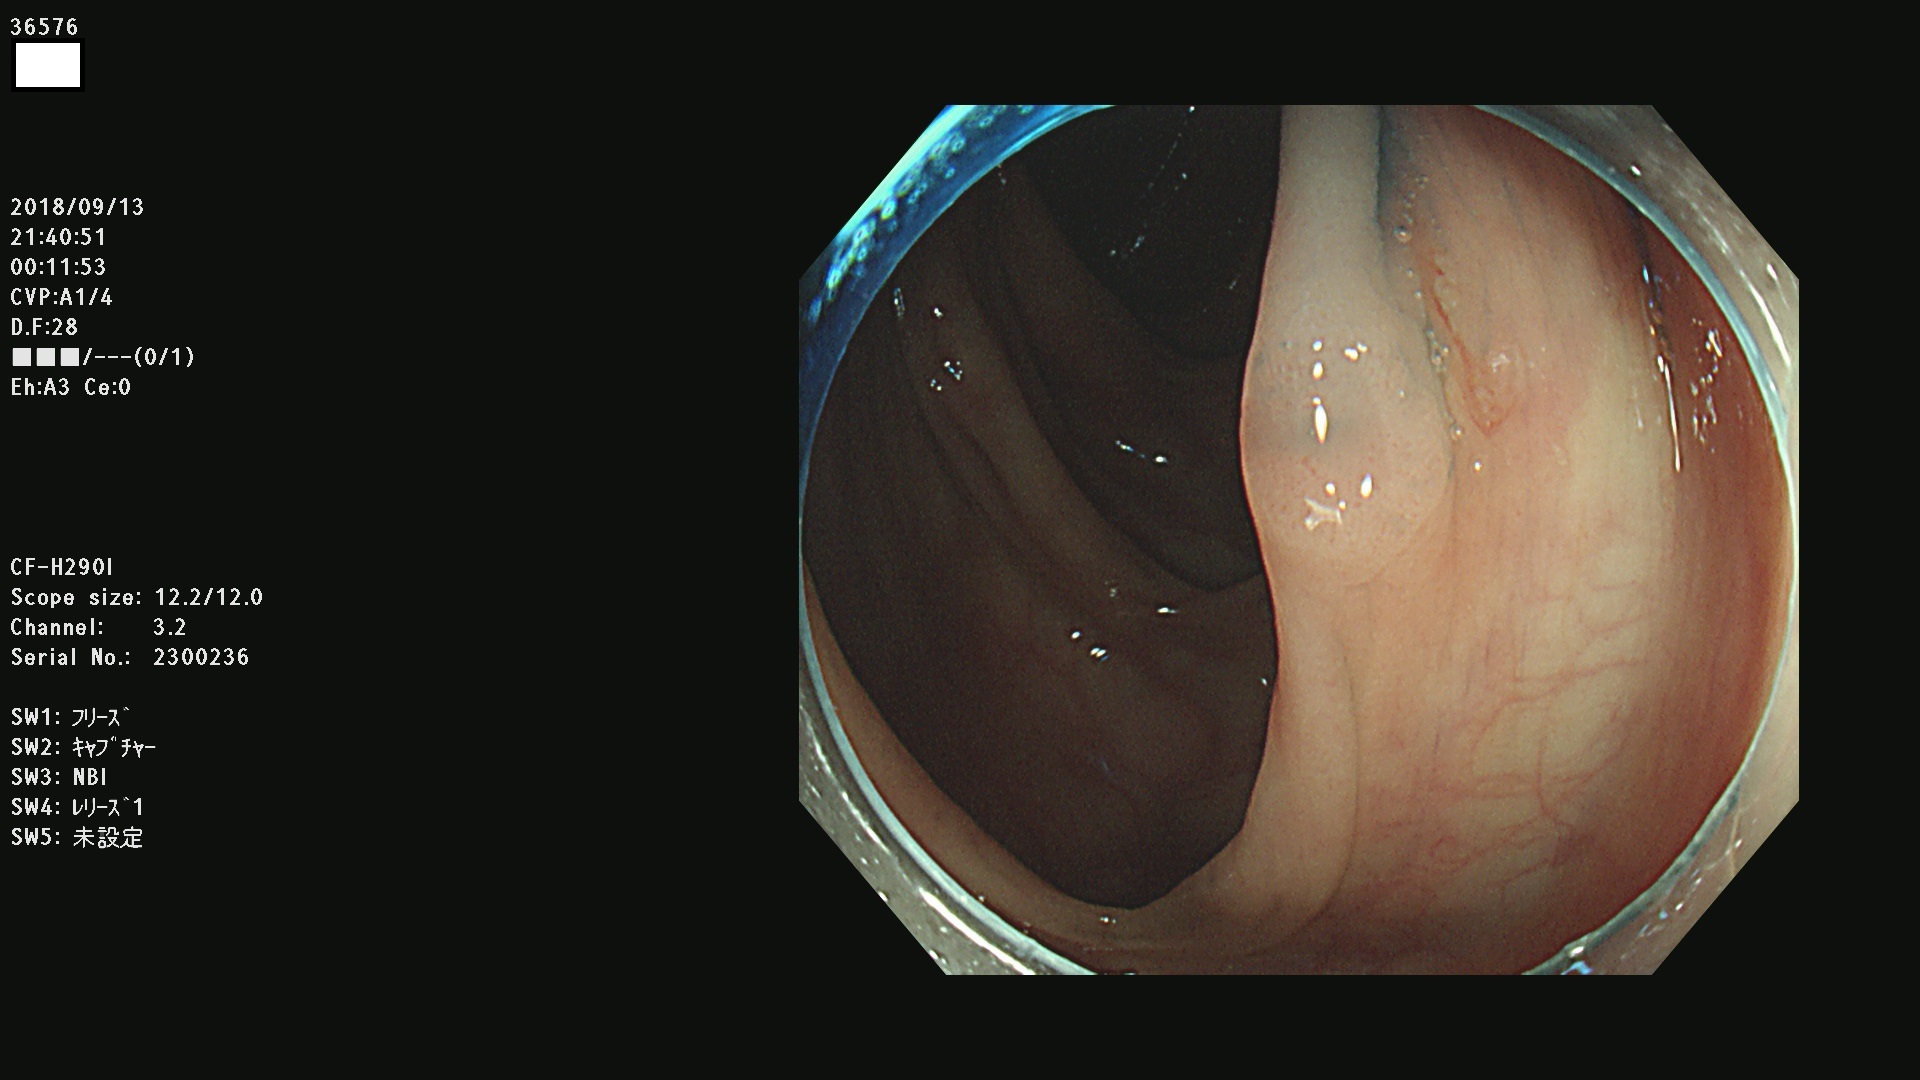

36500 36503 36504 36505 36507(SSAPのみ) 36508 36509 36510 36511 36514 36515 36517 36518 36520 36522(SSAPのみ) 36523 36524 36526 36528 36530 36531 36532 36533 36534 36535 36536 36538 36541 36542 36543 36544 36545 36546 36548 36550 36551 36554 36555 36556 36558 36559 36560 36561 36564 36565 36567 36568 36570 36572 36573 36574 36575 36576 36577 36578 36579 36580 36582 36584 36586 36591 36592 36593 36594 36595 36596 36597 36598

発見困難で危険性の高い平坦型病変(上記100名より抽出)